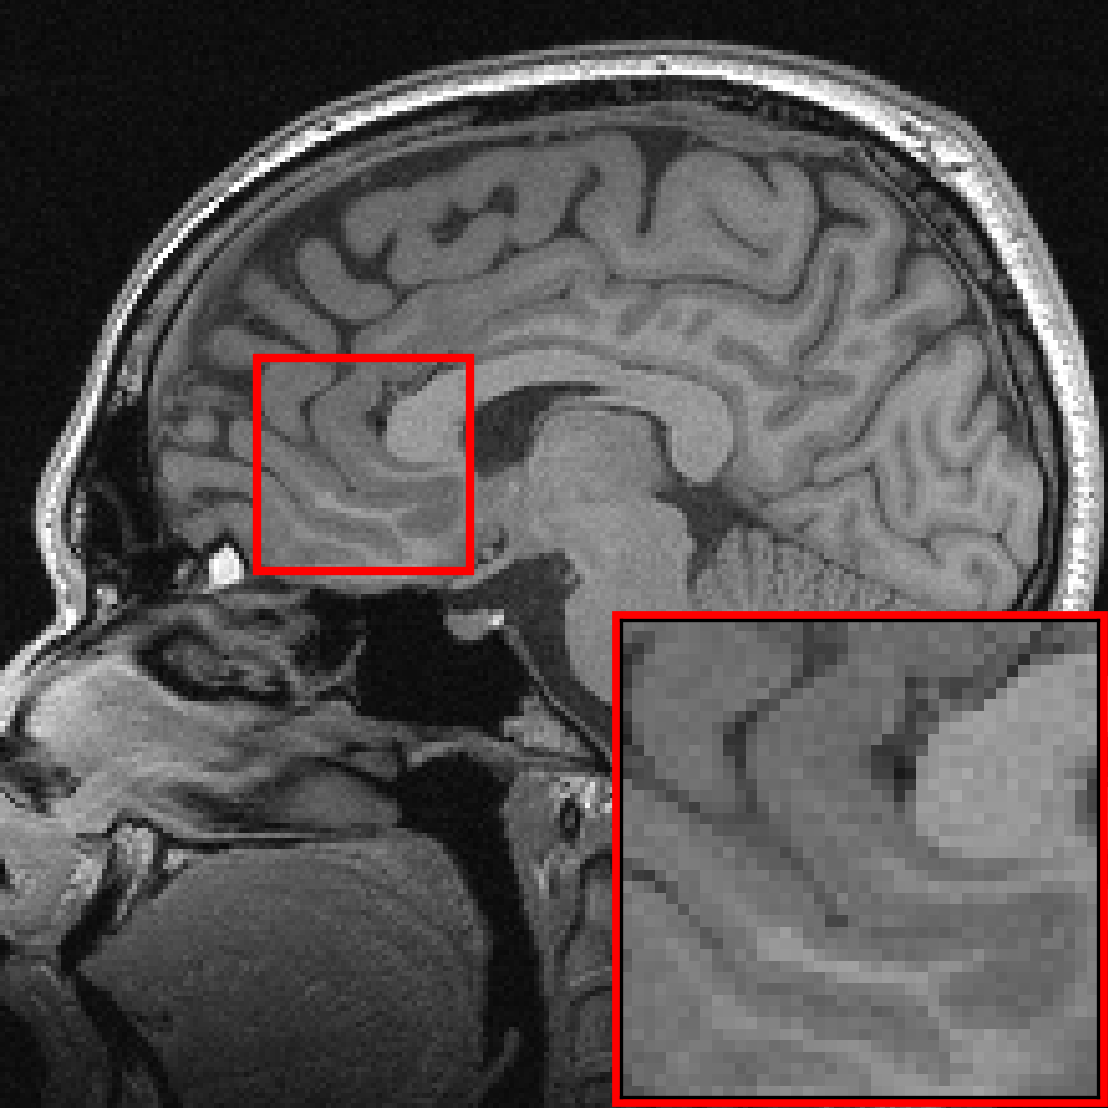

Many of our experiments are based on splits of the fastMRI dataset \citepzbontarFastMRIOpenDataset2019a, the most commonly used dataset for MRI reconstruction research. Figure 2 depicts samples from the fastMRI dataset and shows that MRI data vary in appearance across different anatomies and image contrasts (T1, T2, etc.). The image distribution also varies across vendors and magnetic field strengths of scanners, as the strength of the magnet impacts the signal-to-noise ratio (SNR), with stronger magnets leading to higher SNRs.

The fastMRI dataset stands out for its diversity and size, making it particularly well-suited for exploring how different data distributions can affect the performance of deep learning models for accelerated MRI. In our experiments in Section 3, 4, 5, and 6 we split the fastMRI dataset according to different attributes of the data. In Section 7, we showcase the generalizability of our findings on a diverse collection of 17 different datasets.

We consider two distributions and , and train U-nets \citepronnebergerUNetConvolutionalNetworks2015a, ViTs \citepdosovitskiyImageWorth16x162021b and end-to-end VarNets \citepsriramEndtoEndVariationalNetworks2020b on data from distributions and on data from distribution separately. We also train the same models on data from and , i.e., . We then evaluate on separate test sets from distribution and . We consider the end-to-end VarNet because it is a state-of-the-art model for accelerated MRI, and consider the U-net and ViT as popular baseline models. This diverse selection of architectures (unrolled, convolutional, transformer) aims to demonstrate that our qualitative results are independent of the specific architectural choice. We consider the following choices for and , which are subsets of the fastMRI dataset specified in Figure 2:

Anatomies. are knees scans collected with 6 different combinations of image contrasts and scanners and are the brain scans collected with 10 different combinations of image contrasts and scanners.

We are given data from two distributions and , where distribution can be split up into sub-distributions . We consider the following choices for the two distributions, all based on the knee and brain fastMRI datasets illustrated in Figure 2:

Anatomy shift: is knee data collected with all 6 different combinations of image contrasts and scanners, and are the different brain datasets collected with 8 different combinations of image contrasts (FLAIR, T1, T1POST, T2) and scanners (Skyra, Prisma, Aera, Biograph mMR).